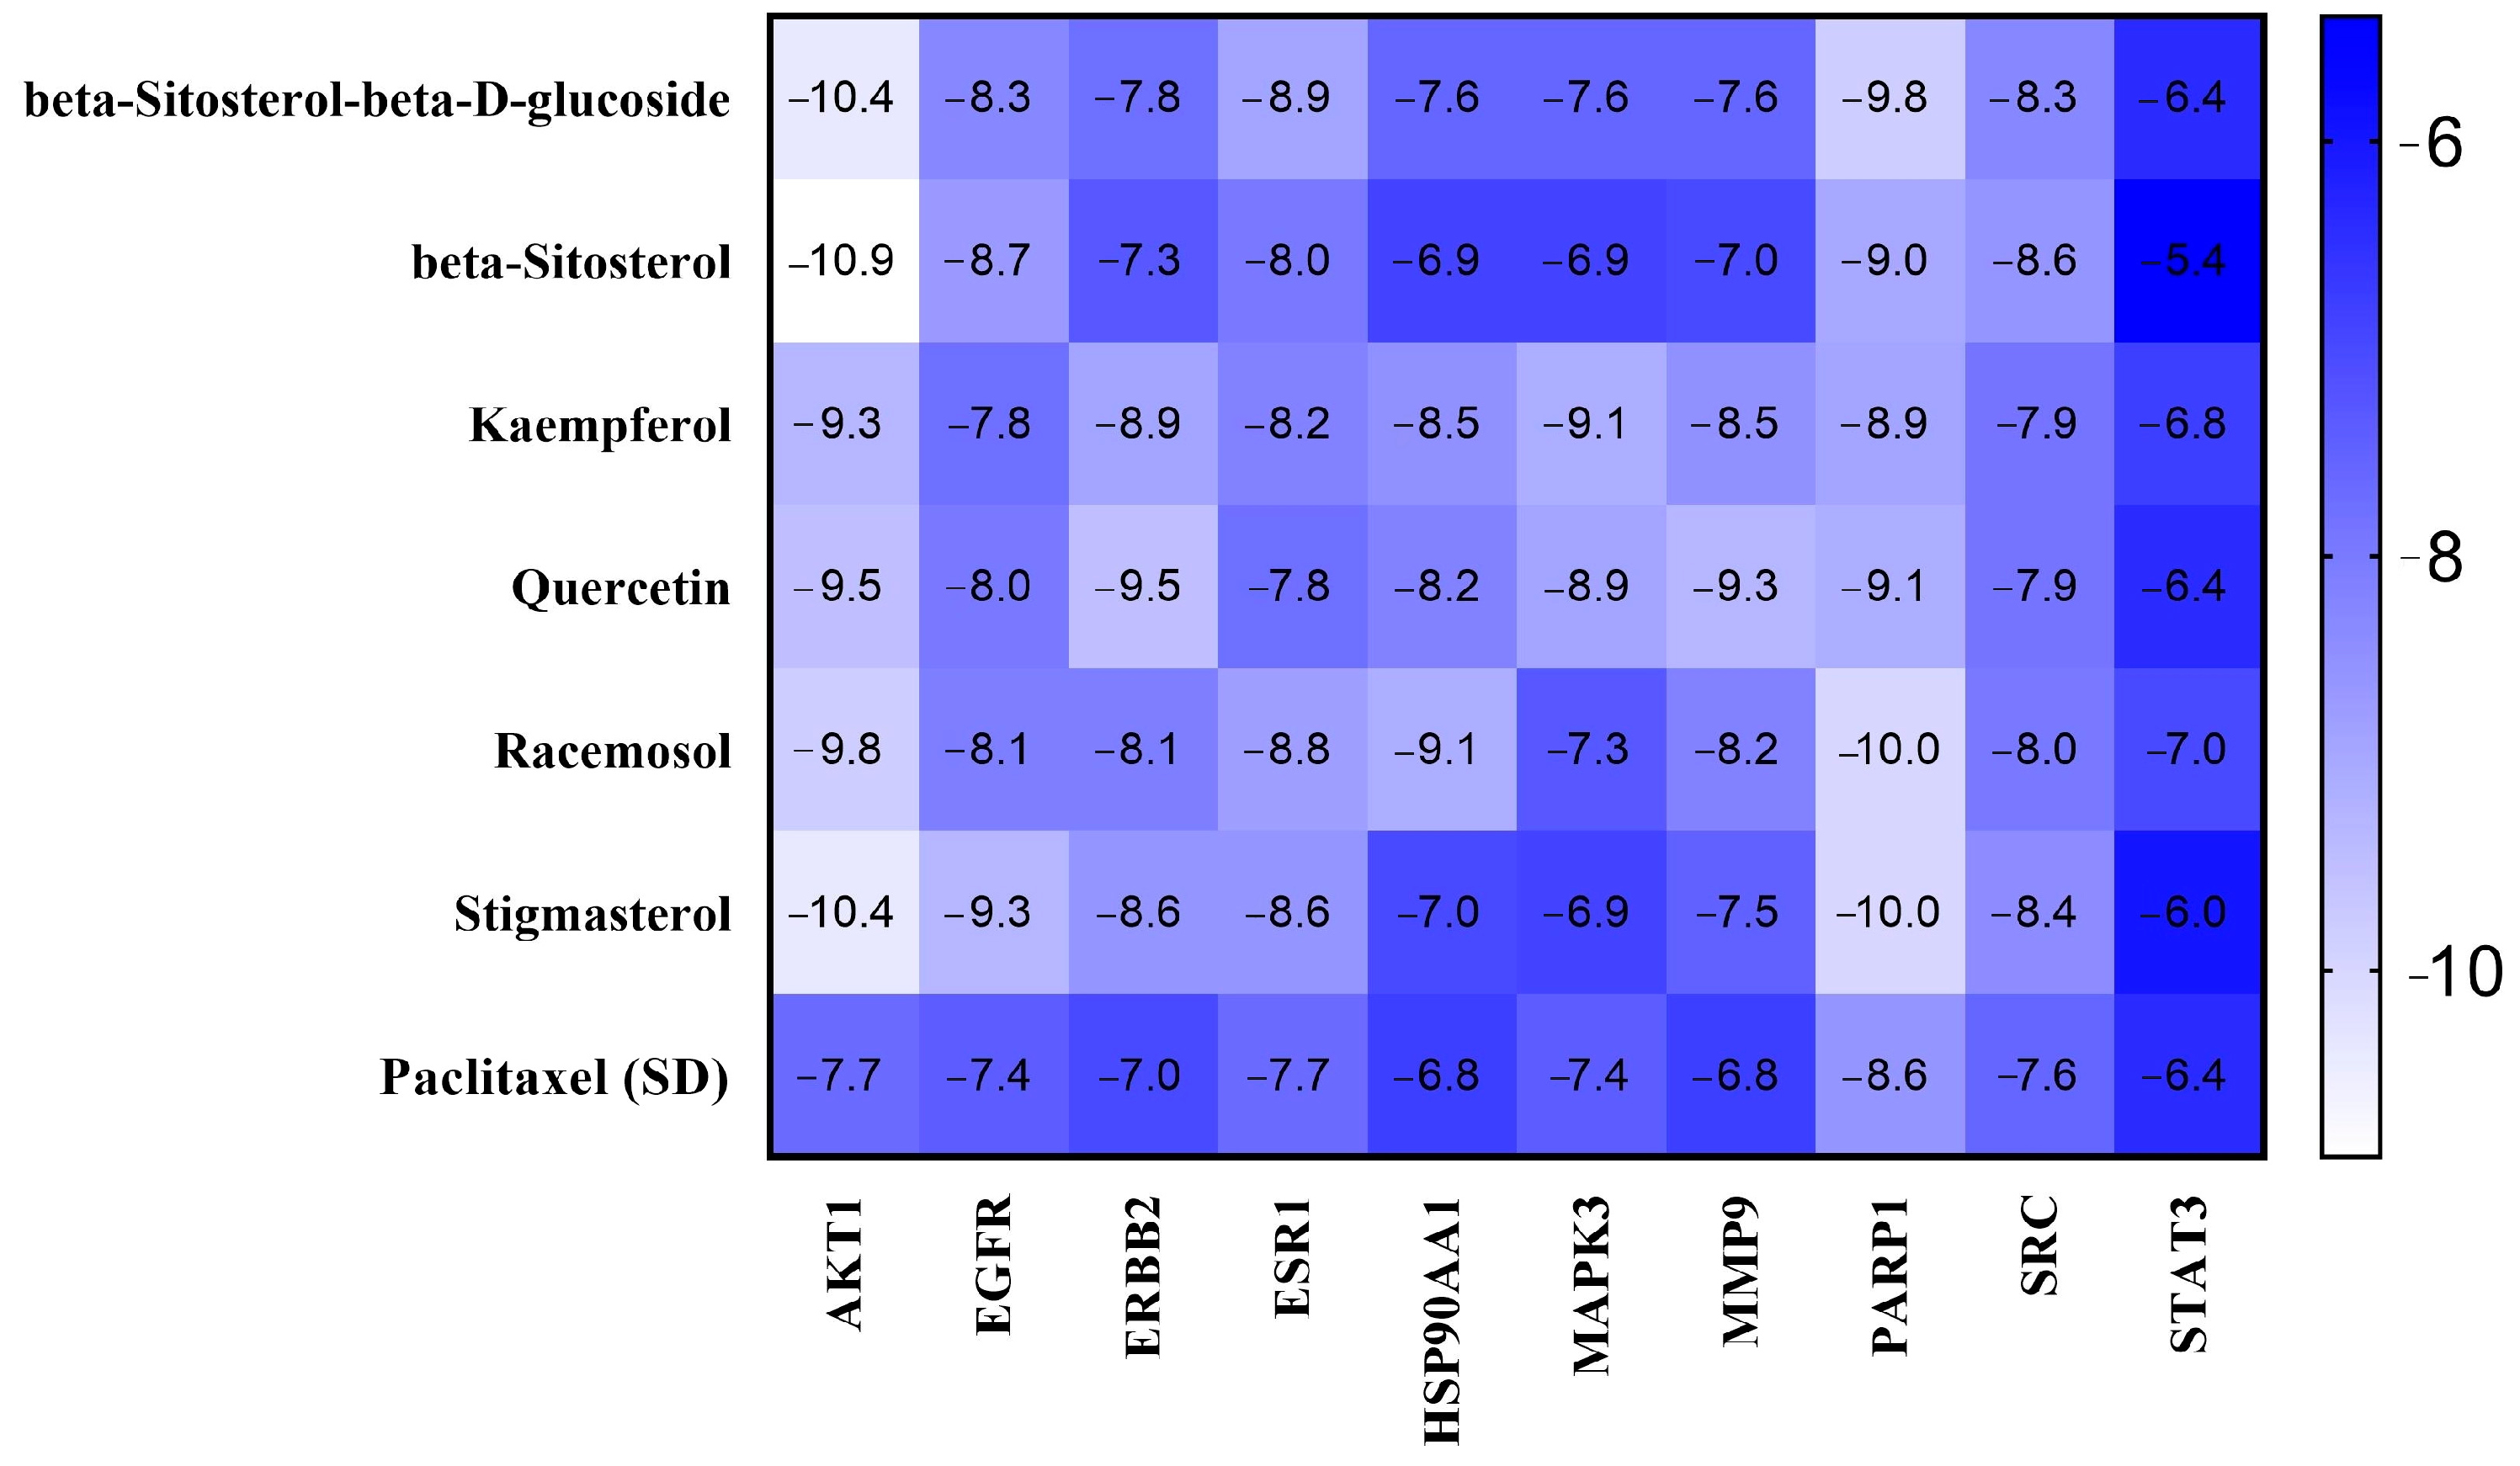

2.5. Binding Affinity and Molecular Interaction Analysis

4.6. Molecular Docking Studies